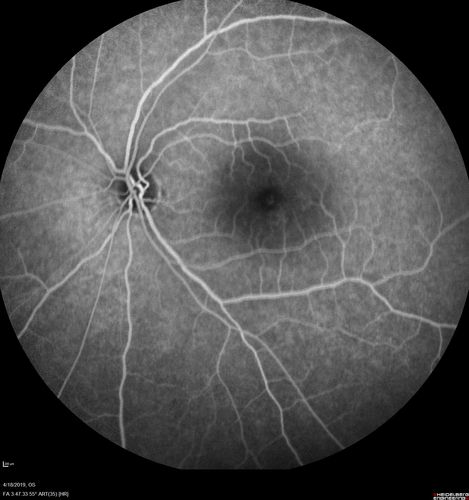

Central Serous Chorioretinopathy - Moderate

49 year old man with episodes in 2011, 2017, and 2018 - now with some paracentral vision loss in the right eye and subretinal fluid.

Chronic Moderate Central Serous Chorioretinopathy